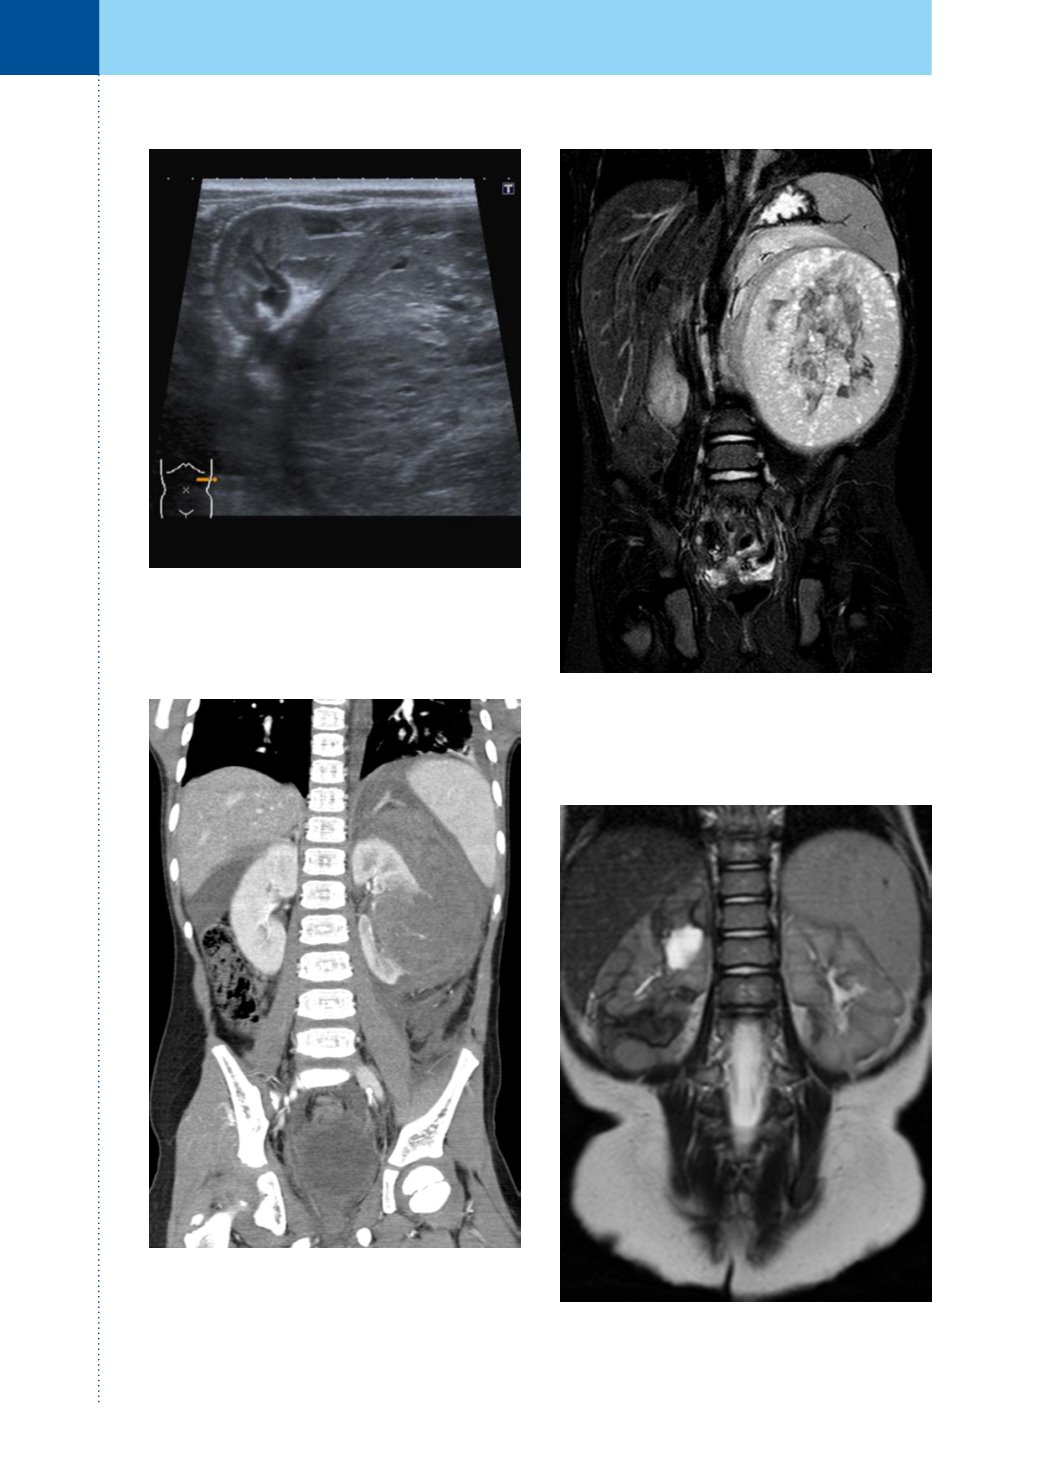

Obr. 2.

Ultrazvuk; nefroblastomdolního pólu ledviny

vlevo

Fig. 2.

Ultrasound; nephroblastoma of left kidney

(Wilms‘ tumor)

Obr. 3A.

CT koronálně rekonstrukce; ruptura

nefroblastomu ledviny vlevo

Fig. 3A.

CT scan coronal reconstruction; rupture of

left kidney nephroblastoma

Obr. 3B.

MR koronálně, STIR; nefroblastom levé

ledviny

Fig. 3B.

MR scan STIR; nephroblastoma of left kidney

Obr. 3C.

MR koronálně, T2 TSE; nefroblastomatóza

Fig. 3C.

MR scan, T2 TSE; nephroblastomatosis